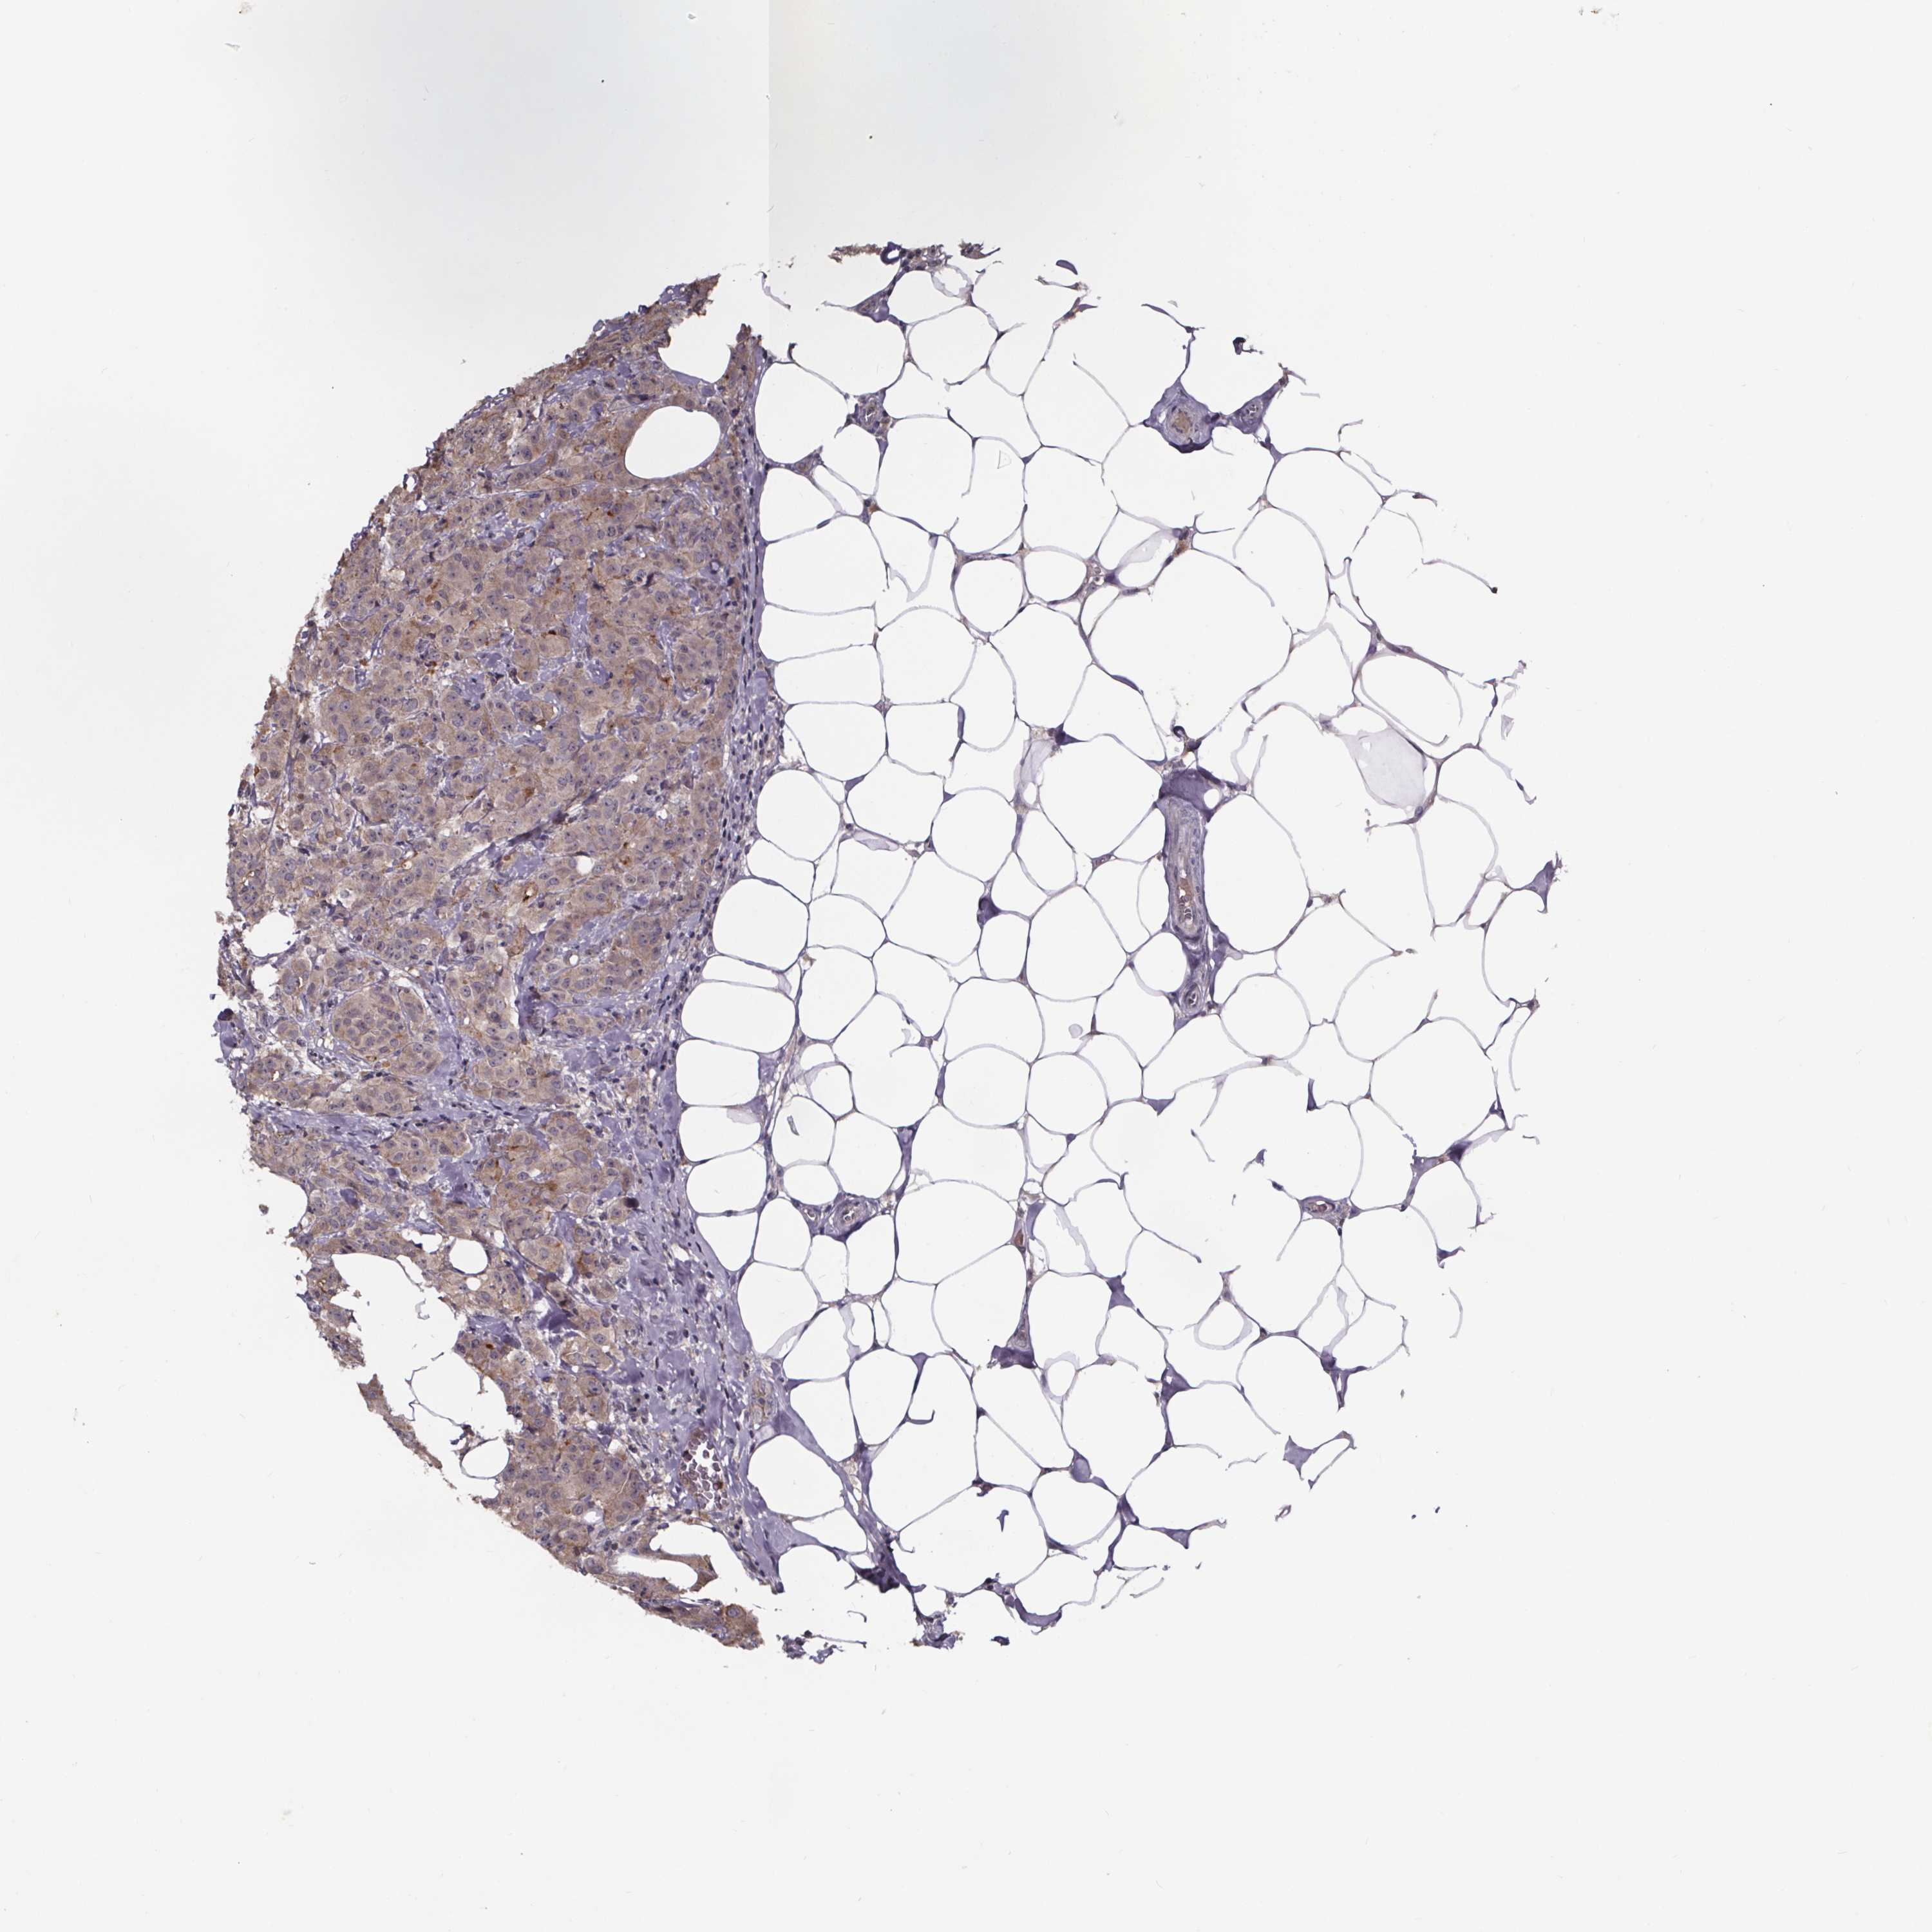

CANCER BREAST CANCER Show tissue menu

Breast cancer

Human cancer

Breast invasive carcinoma